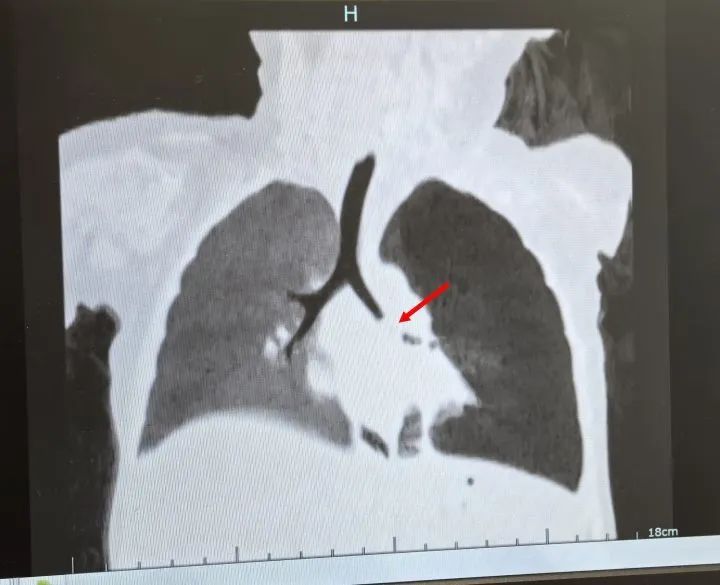

在呼吸内科门诊,洋洋做了检查——肺炎支原体IgM 弱阳性,是支原体感染?可是胸片显示,右肺明显的透亮度增高,事情看起来不那么简单。经验丰富的医生立即安排了肺部CT检查,结果在右肺主支气管里发现了异物堵塞,并且已经导致了对侧肺炎!

医生不敢掉以轻心,立即安排肺部CT检查,结果发现左肺主支气管可见巨大的占位,而且左肺气肿得厉害,这次又会是什么?呼吸内镜团队再次“披挂上阵”。气管镜下,映入眼帘的竟然是硕大的肉芽样物,几乎完全堵塞了气道,一碰就出血,异物却没见到。